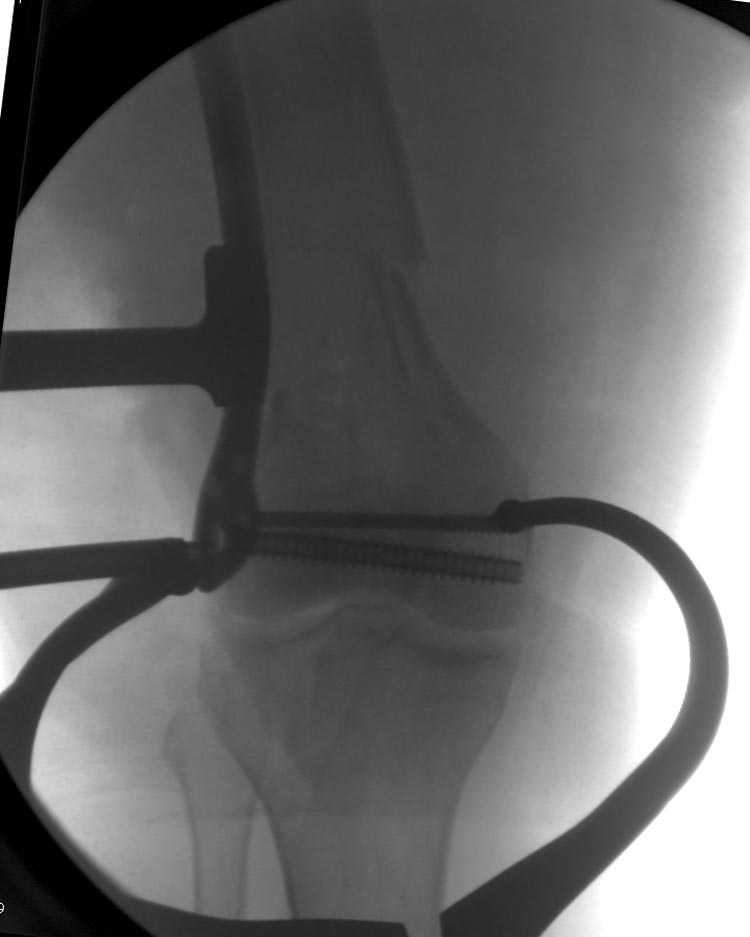

Смело открывайте сустав, собирайте мыщелки на один спонгиозник или болт стяжку и под него вводите штифт из стандарного места введения. В данном случае хорошо подойдет универсальный бедренный штифт СнМ.

Бесспорно, предлагаемый ретроградный метод имеет свои преимущества, но имеется опасность при манипуляции интрамедуллярным гвоздем расколоть мыщелки.

Раскол можно предупредить шурупами, но короткий дистальный фрагмент навряд ли позволит добиться адекватной стабильности конструкции. Стандартные гвозди не рассчитаны для таких переломов, и если все таки желаете провести фиксацию гвоздем, тогда надо заказывать специальный custom made nail т.е. с расширенной возможностью дистальной блокировки.